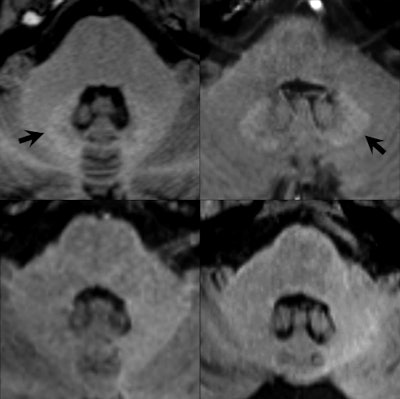

Gadolinium is a toxic heavy metal not normally found in the body, but when chelated to reduce toxicity, it becomes a powerful contrast agent for MRI scans and has improved the imaging of body organs and tissues. It has been used successfully for many years, but over the past decade has been linked to nephrogenic systemic fibrosis (NSF), which involves the thickening and scarring of skin and internal organs. Also, some gadolinium-based contrast agents (GBCAs) have been found to undergo dechelation, resulting in gadolinium deposits in the brain and other body tissue.

Olchowy, who will be speaking in today's session on assessing brain tissue damage caused by gadolinium deposition, said there was still a question mark over the possible clinical implications of deposition.